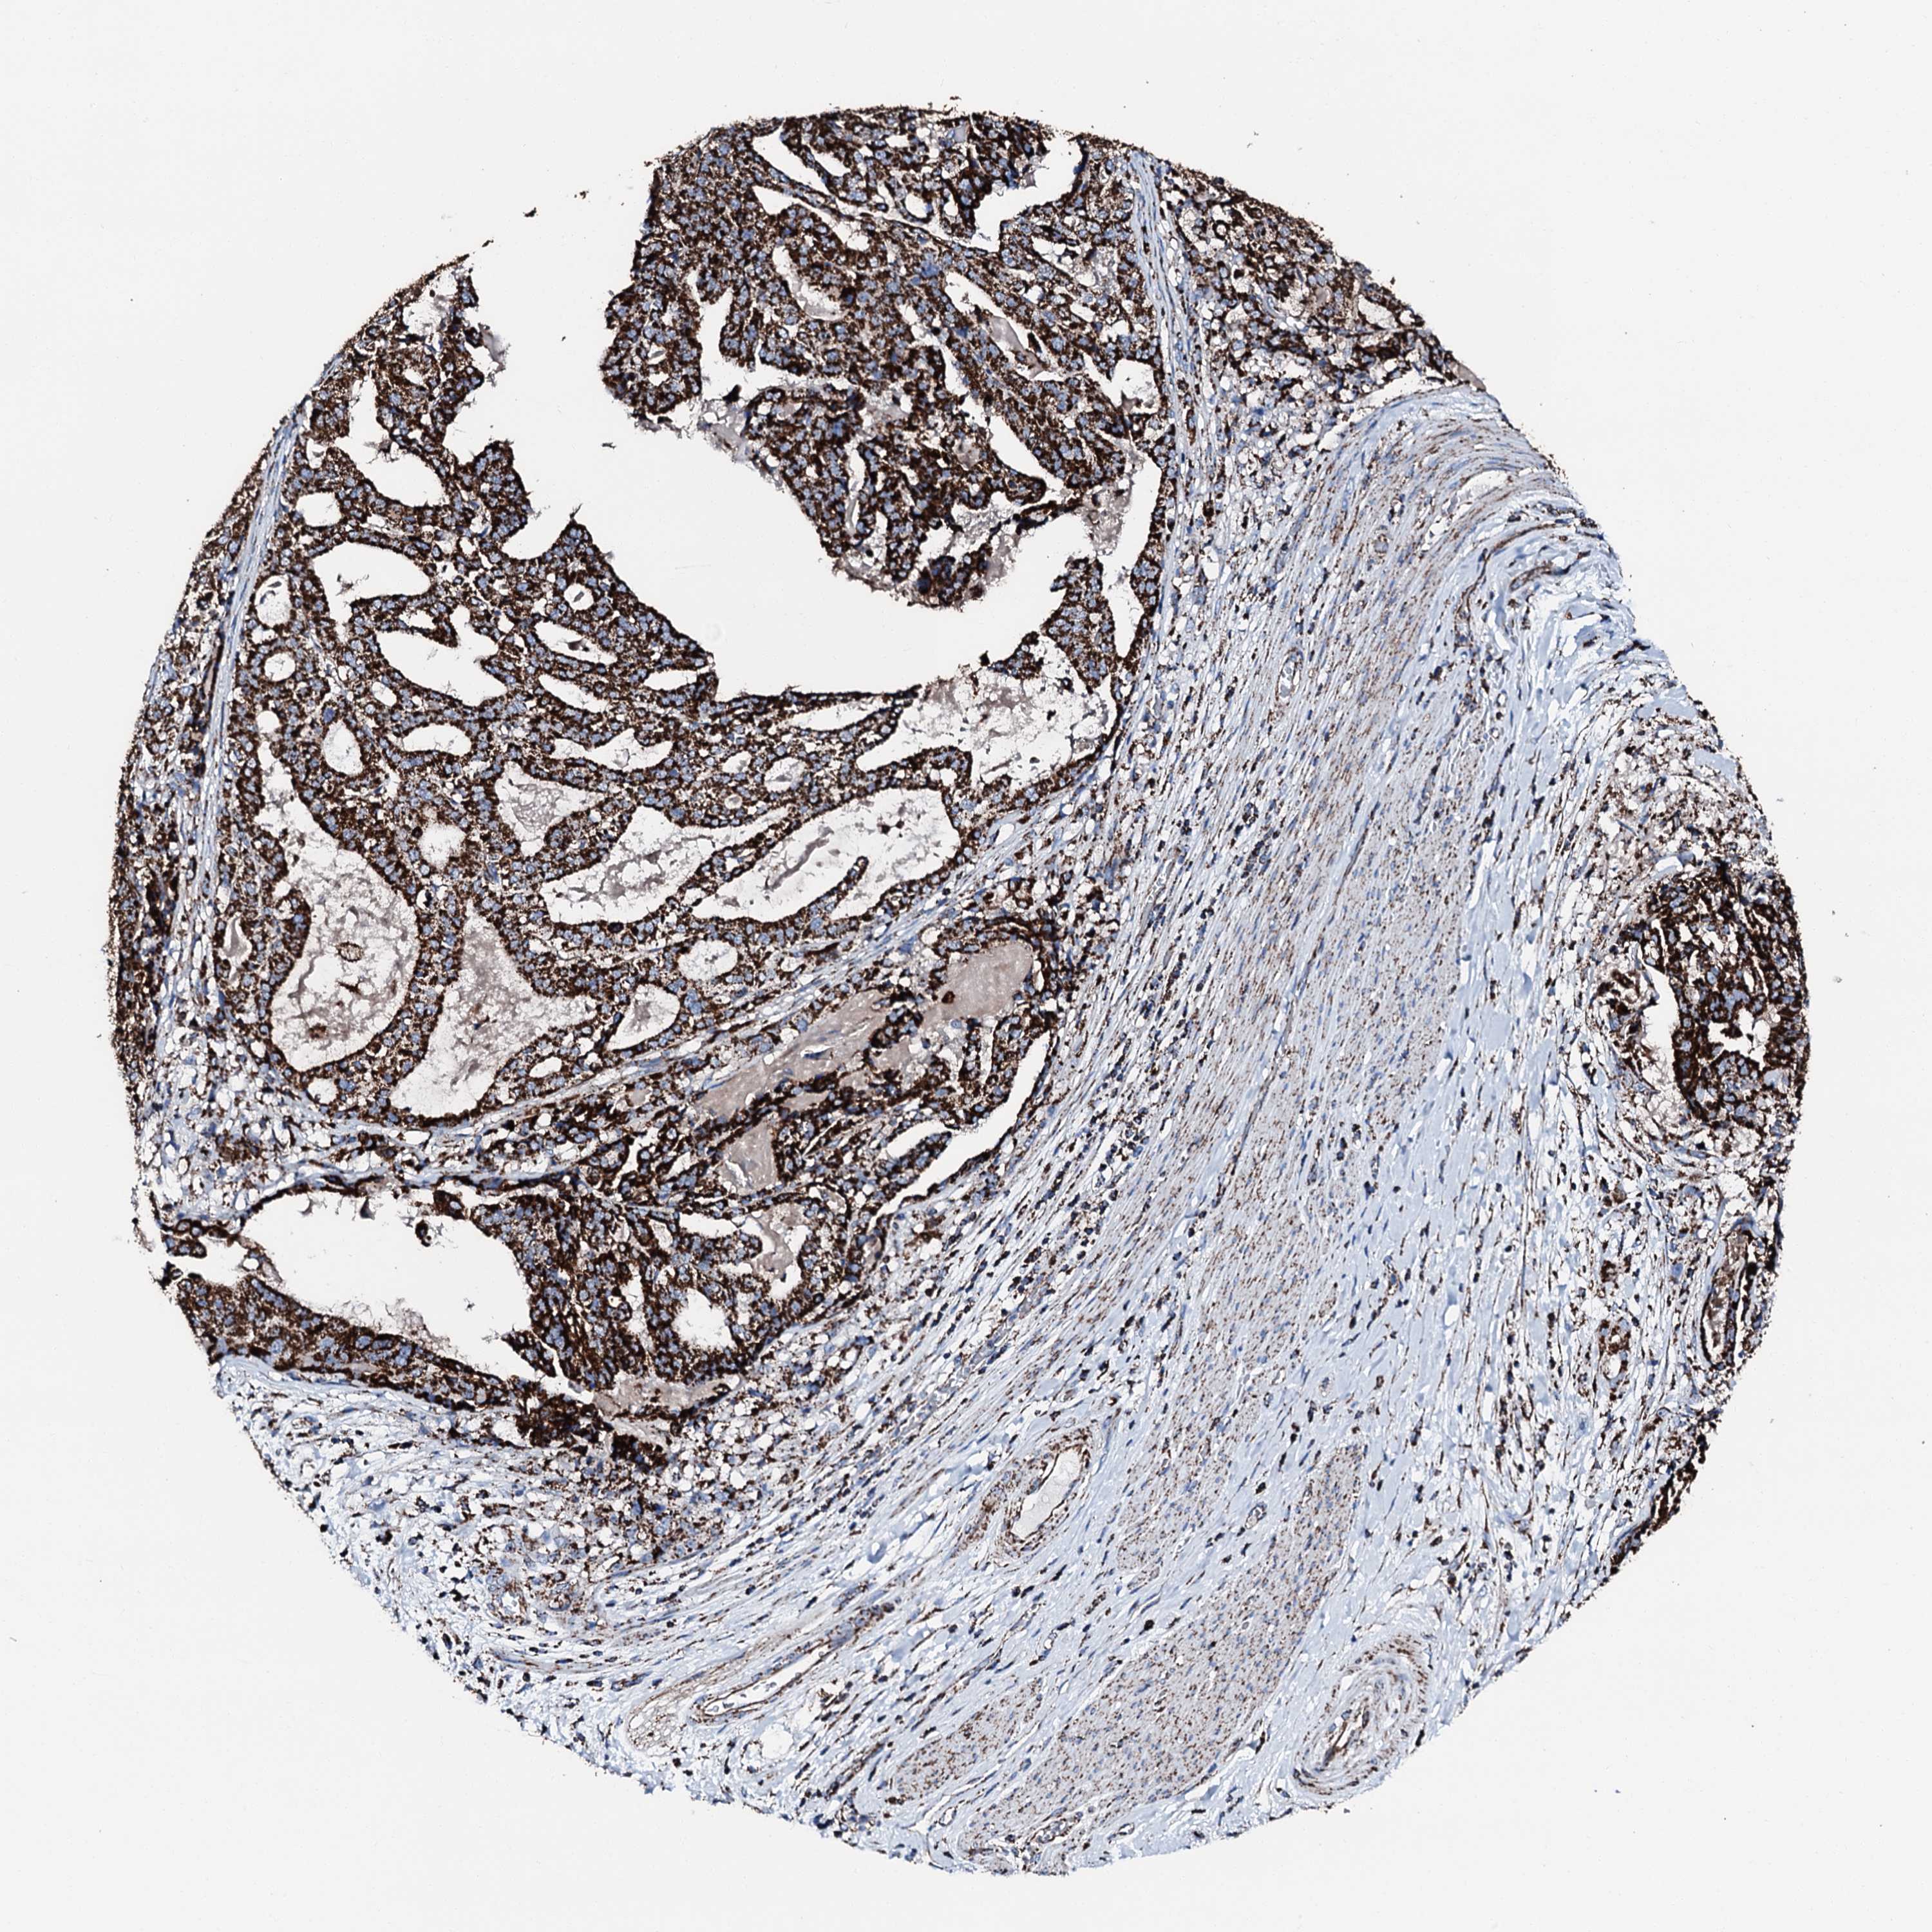

STOMACH CANCER - Protein expressioni

A mouse-over function shows sample information and annotation data. Click on an image to view it in a full screen mode. Samples can be filtered based on level of antibody staining by selecting one or several of the following categories: high, medium, low and not detected. The assay and annotation is described here.

Note that samples used for immunohistochemistry by the Human Protein Atlas do not correspond to samples in the TCGA dataset.

Antibody stainingi

Antibody staining in the annotated cell types in the current human tissue is reported as not detected, low, medium, or high, based on conventional immunohistochemistry profiling in selected tissues. This score is based on the combination of the staining intensity and fraction of stained cells.

Each image is clickable and will lead to virtual microscopy that enables deeper exploration of all samples and also displays staining intensity scores, fraction scores and subcellular localization as well as patient and tissue information for each sample.

Antibody HPA039588

Antibody HPA043888

Staining

High

Medium

Low

Not detected

Intensity

Strong

Moderate

Weak

Negative

Quantity

>75%

75%-25%

<25%

None

Location

Nuclear

Cytoplasmic/membranous

Cytoplasmic/membranous,nuclear

Adenocarcinoma, NOS